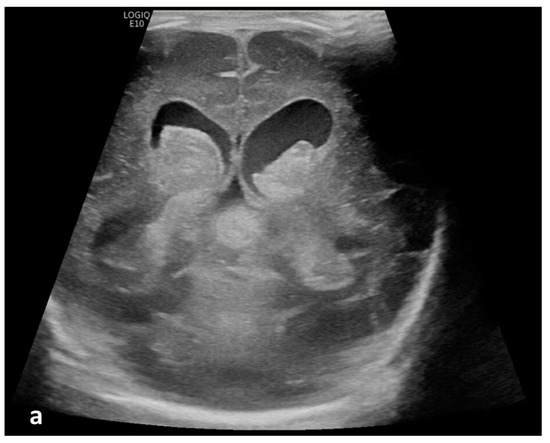

Twenty patients (19.8%) demonstrated apparent CSF flow detectable using MVI in at least one of the ventricular structures: 11 (10.9%) in the third ventricle, 16 (15.8%) in the cerebral aqueduct, and 17 (16.8%) in the fourth ventricle (Figure 1 and Figure 2). Of these 20 patients, 13 had IVH as visualized in grayscale US; flow direction was detected as craniocaudal in 15% (n = 3) of patients, caudocranial in 70% (n = 14), and bidirectional in 15% (n = 3) (Supplemental S1 and S2; Table 1). The IRR for detection of CSF flow was 0.662, p < 0.001.

Figure 2.

Cerebrospinal fluid (CSF) flow visualized in a patient with post-hemorrhagic hydrocephalus. A 7-day-old boy with a history of severe intraventricular hemorrhage and ventriculomegaly. Coronal and sagittal grayscale ultrasound shows enlargement in the lateral and third ventricles, as well as evolving choroid plexus hemorrhage and fine granular mobile debris in the ventricles (a–c). The parenchymal evaluation shows grade IV left parieto-occipital periventricular hemorrhage (c). Sagittal B-Flow (d–f) demonstrates turbulent caudocranial CSF flow from the cerebral aqueduct (arrows) into the third ventricle (dotted arrows). The entire clip is provided as Supplemental Material S2.